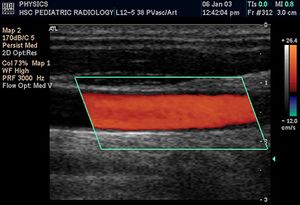

التخطيط الصدى الدوپلري

تكون الصورة عادةً ملونة، فيظهر الدم اما بلون أحمر أوأزرق حسب اتجاه الجريان بالنسبة للمجس الفاحص. ويقدم الجهاز معلومات ممتازة في تقييم صمامات القلب وارتفاع الضغوط الدموية في الأوعية الدموية.

تحليل لسرعة جريان الدم بالأوعية.